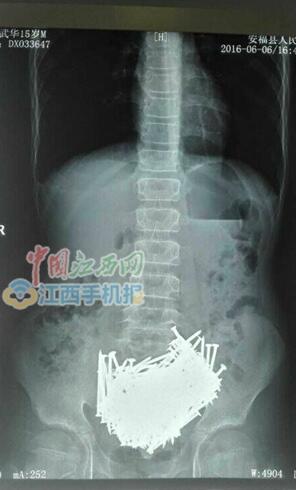

医生从男子的胃里取出200余枚钉子

CT检查结果

中国江西网吉安讯记者彭南报道:近日,中国江西网记者获悉,安福县金田乡15岁少年小刘,因身体不适被家人送医检查,CT检查后惊呆了医生,胃里一堆钉子,手术后取出200多颗钉子,还有牙签、石头、硬币等,共重约700克。